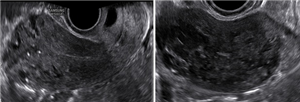

Thai ngoài tử cung mạn tính (TNTCMT) là một thể hiếm gặp của thai ngoài tử cung ở tai vòi